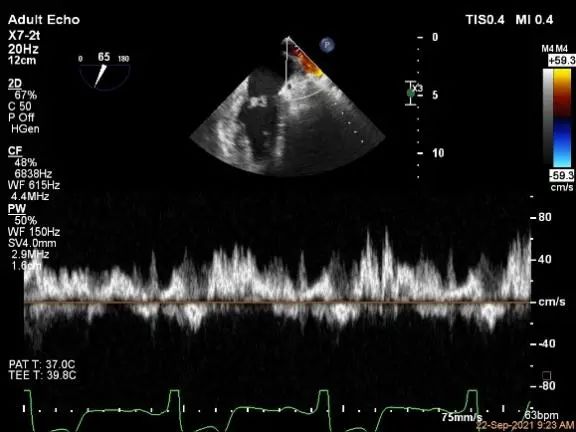

P2区脱垂,宽14.8mm,Gap:3.3mm

3D-color,返流重度,3+级

麻醉状态下左肺静脉血流频谱

MVA:6.67cm²